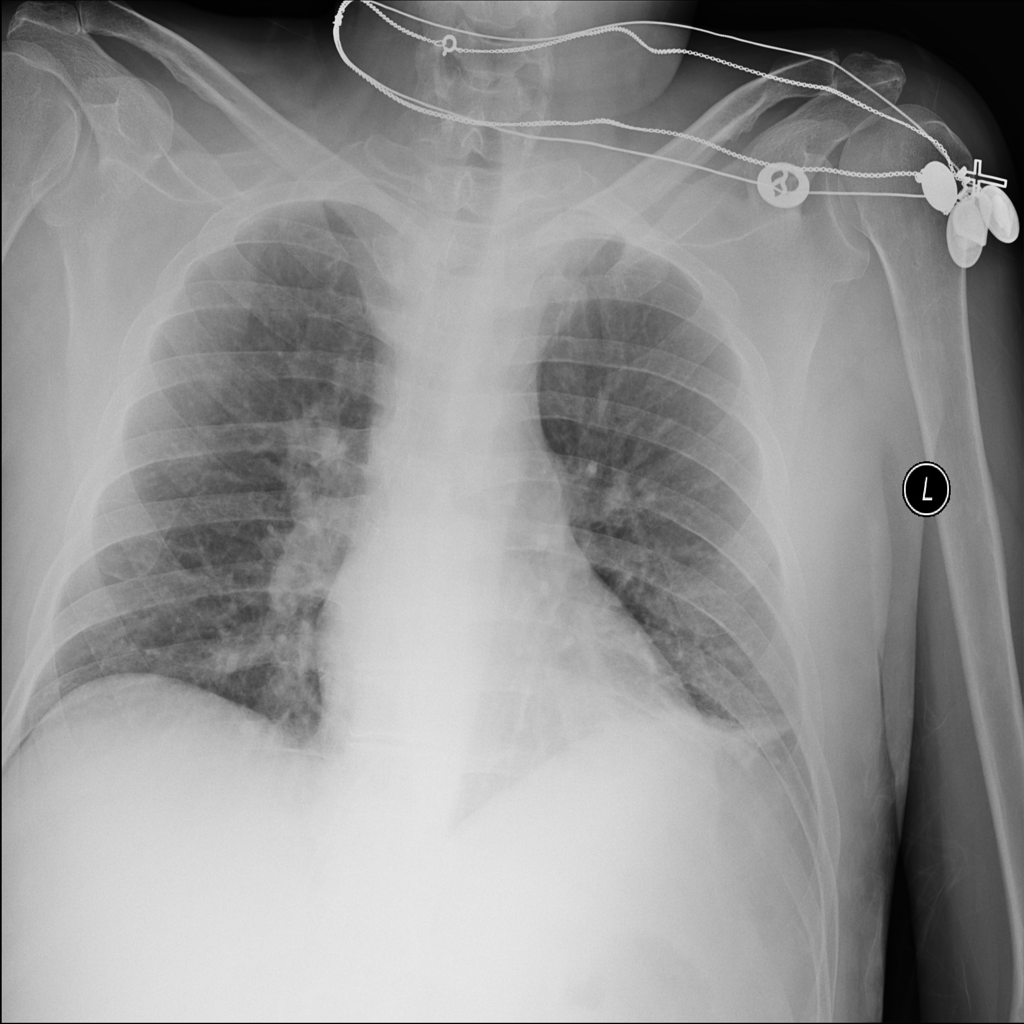

PAT-DB80 · IMG-000Atelectasis

PAT-DB80 · IMG-000

PA